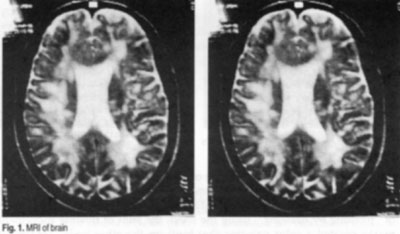

On admission: massive cerebellar ataxia, unable to drink or eat on her own. Spontaneous, image-directed nystagmus in all directions. Scanning speech, severest degree of dysarthrophonia. Spastic tetraparesis, severest degree of ataxia in extremities; unable to sit unsupported, walk or stand. MRI showed marked, florid episode of disseminate encephalomyelitis with multiple CM-receptive foci in the CNS.

Fig. 1.MRI of brain

In view of the extreme immobility that led to the patient's admission just under a year ago, with massive inflammatory changes in form of CM-receptive foci in the CNS, the evolution so far may be said to have been extremely good.